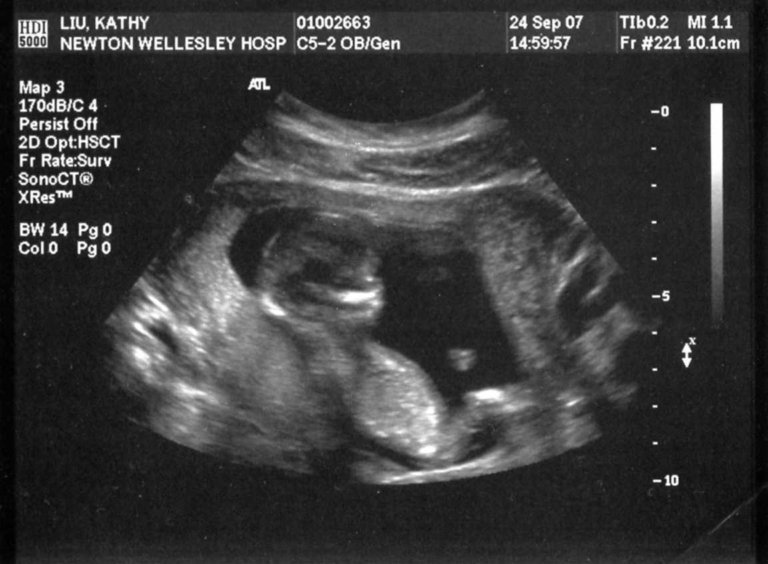

This is from the first set of ultrasound pictures taken by the Maternal-Fetal Medicine group at Newton-Wellesey Hospital. The ultrasounds are part of the "integrated screening" - they checked the ratios of arm and leg bones, etc. to look for signs of Downs Syndrome and other genetic diseases. They also took a blood sample from Kathy for genetic testing. Luckily, we "passed" the test (tested negative) for most genetic diseases but the risk of Downs was assessed at about 1 in 270 (mostly due to Kathy's age), so a follow up appointment was scheduled for the following month.

Jon says this picture shows that the baby is definitely his - it looks like she is leaning back with one arm behind her head and one arm out with the remote :)